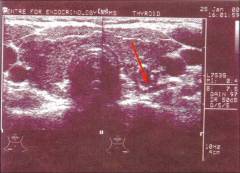

УЗИ щитовидной железы

Этот дешевый, доступный и безболезненный метод позволяет получить информацию о размере щитовидной железы, ее состоянии, однородности, кровоснабжении, а также выявить изменения в шейных лимфатических узлах.

УЗИ позволяет выявить такие признаки узлового зоба:

Если при проведении УЗИ выявлен узел превышающий размером 1 см или человек подвергался действию канцерогенных факторов, то назначают тонкоигольную пункционную биопсию и исследование крови.